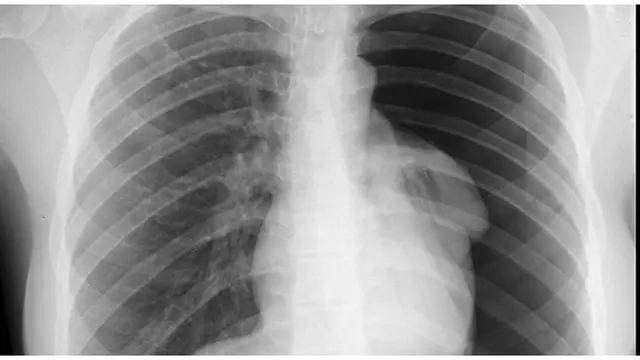

Kondisi paru-paru yang lemah dapat menjadi indikasi COPD atau Chronic Obstructive Pulmonary Disease. Entah apakah anda seorang perokok, mantan perokok atau pun yang merasa sehat-sehat saja, perhatikan sinyal-sinyal masalah paru-paru Anda. Dilansir dari caring.com, berikut 7 tanda paru-paru Anda mengalami masalah serius.

Setiap orang akan mengalami batuk sesekali, tetapi jika Anda merasa Anda terlalu sering batuk dalam sehari dan menjadi kronis, inilah saatnya Anda menemui dokter. COPD dapat mengakibatkan peradangan pada tabung bronkial dan kantung-kantung kecil yang disebut alveoli. Hal ini mengakibatkan kurang fleksibel dan elastisnya tabung bronkial dan alveoli yang melapisi paru-paru. Jika hal ini terjadi, dinding saluran udara akan menebal dan memproduksi lebih banyak lendir dari biasanya. Akibatnya paru-paru Anda akan tersumbat.